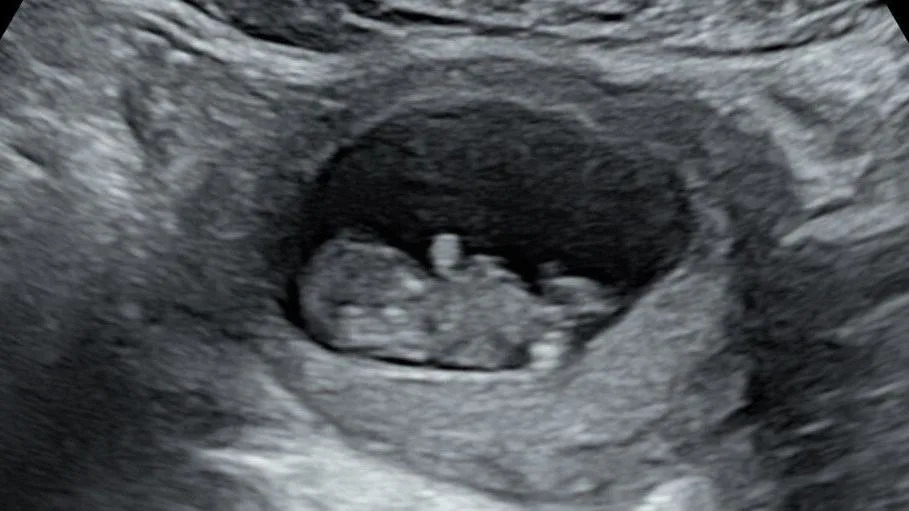

ولكن بعد حدوث نزيف في وقت مبكر، أظهر الاختبار أن ريانون أجهضت في الأسبوع الثامن.

كانت الفحوصات المبكرة للطفل هدسون مطمئنة في البداية لوالدته ريانون [Rhiannon Lawson]

وفي أكتوبر من العام الماضي، اكتشفت أنها حامل مرة أخرى، وتم طمأنتها هذه المرة بإجراء بعض الفحوصات المبكرة.

ولكن بعد ذلك، جاء الفحص الذي استمر 20 أسبوعًا، والذي كشف أن الطفل الرضيع – الذي أطلق عليه الزوجان اسم هدسون – يعاني من شكل حاد من متلازمة القلب الأيسر الناقص التنسج.

وتقول: “لم يكن هناك طريق للمضي قدماً”، وولدت هدسون ميتة في شهر مارس/آذار في الأسبوع 22 من الحمل.